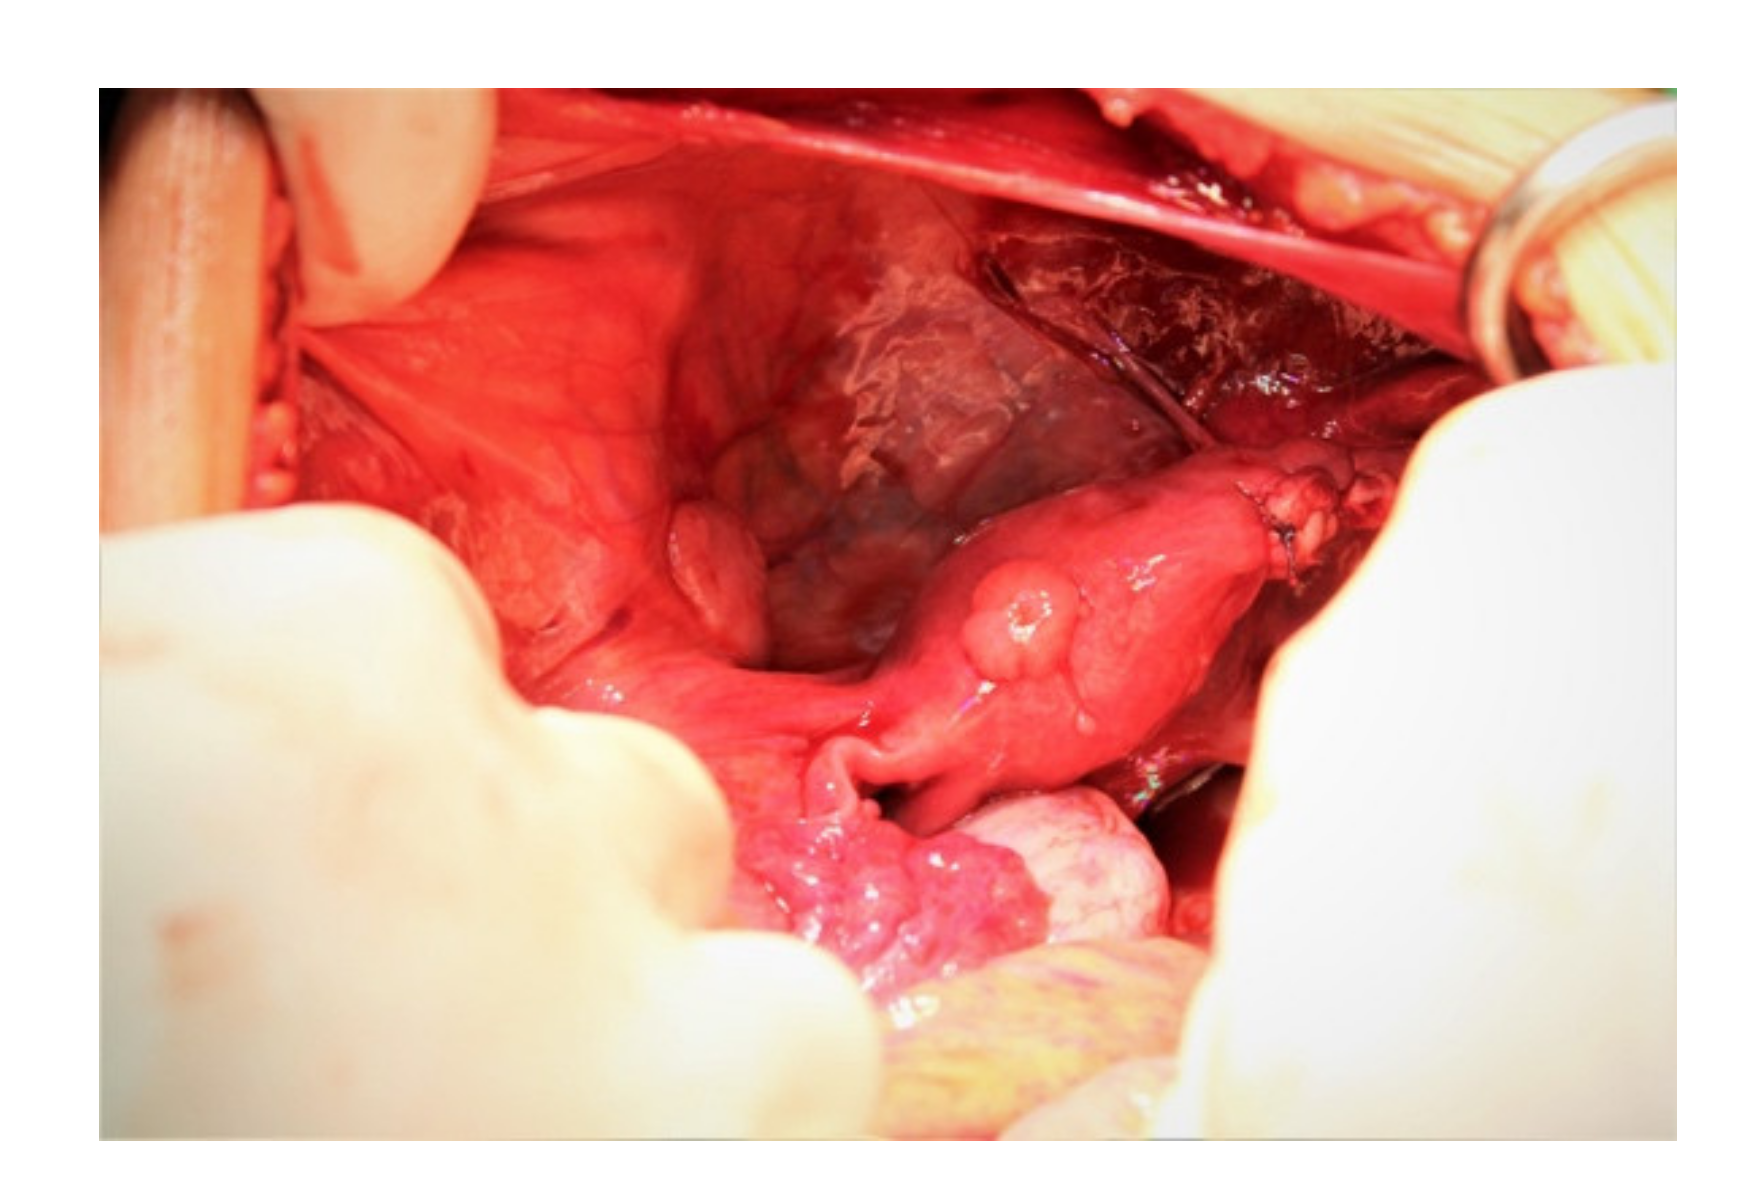

2.1. Dysgerminoma

2.1.1. Macroscopic Features